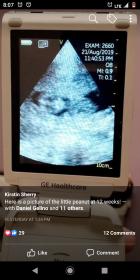

Asking for a friend. It's been long time since I've been on here so no it's not for me but am asking for sister in law she's 12 weeks hoping boy.Attachment 41917